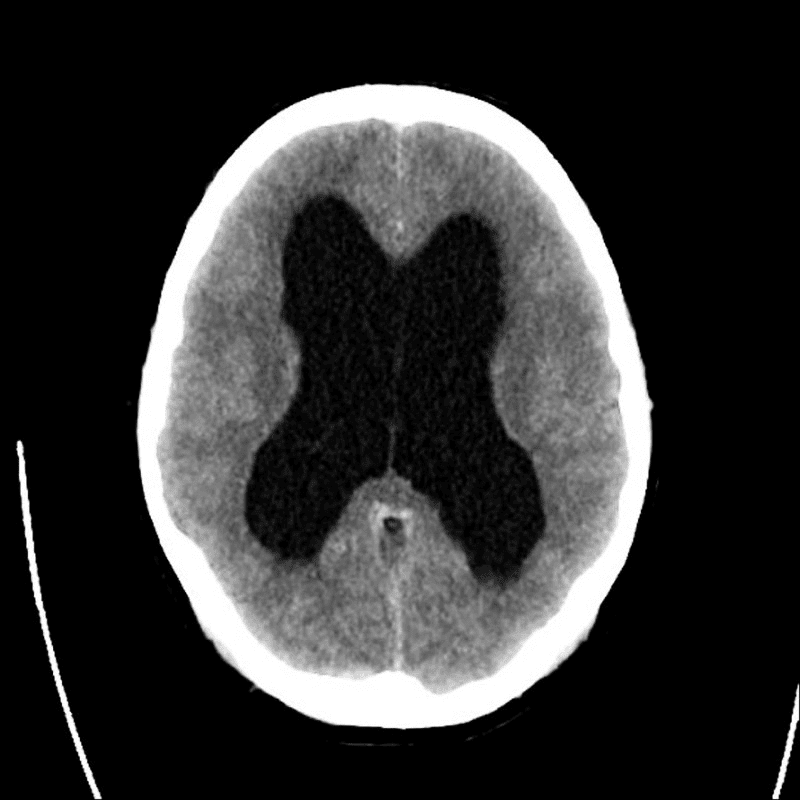

妻子突然被診斷出罕見疾病——水腦症。

這是一種無法根治、只會逐步惡化的神經系統疾病,常見症狀包括:

- 行走困難、平衡障礙

- 尿失禁

- 認知與智能功能退化

- 最終喪失自理能力,需全天候照護